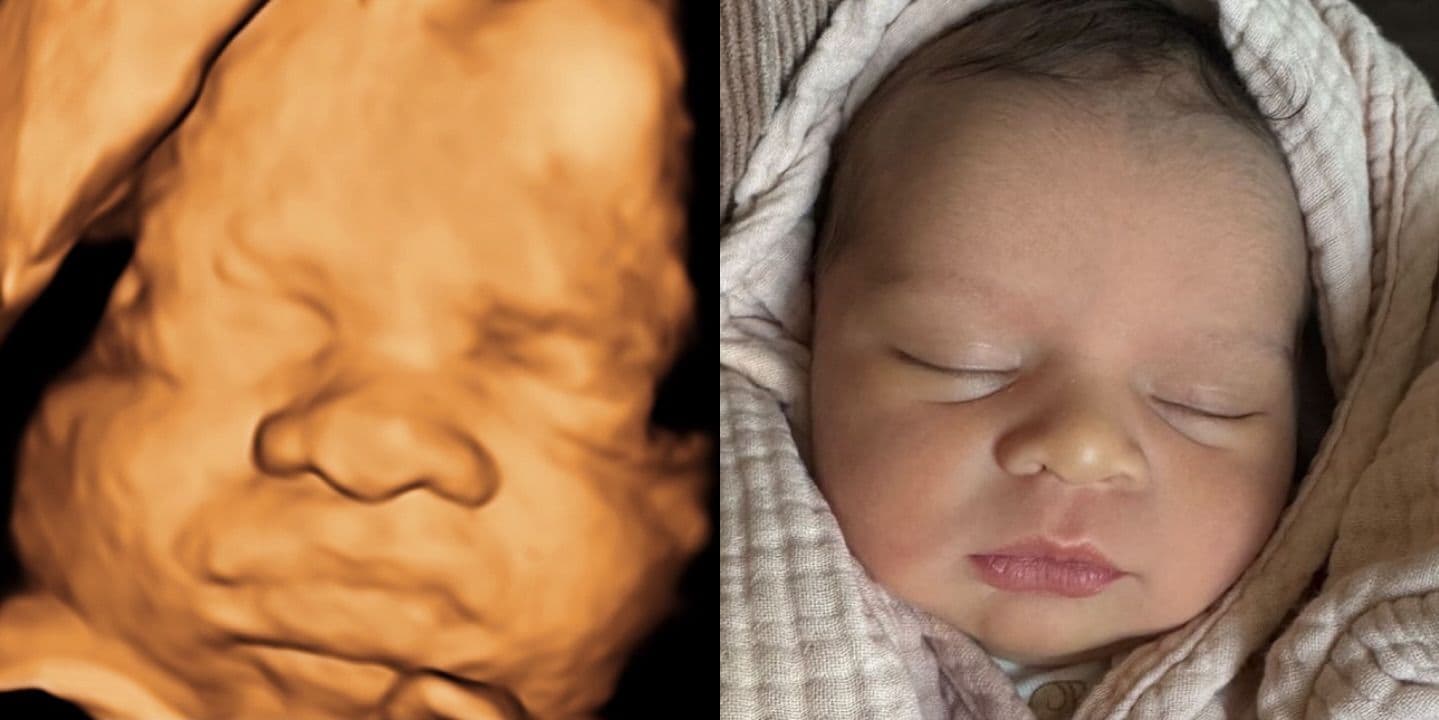

The most common reaction after birth? "The nose looks nothing like the ultrasound." Pregnancy forums are full of parents sharing their 3D ultrasound next to their newborn photo, and the difference is striking. Wide, flat ultrasound noses turn into perfectly normal (often tiny) baby noses.

Ultrasound studios publish before-and-after galleries showing 3D scans alongside the born baby—and you can see the pattern clearly: the nose is almost always wider on the scan. Browse real examples at Fetal Vision Imaging, 3D Baby Boutique, and Baby Moments Ultrasound. Not every case is dramatic—some noses match closely—but the wide-nose effect is by far the most common outcome.